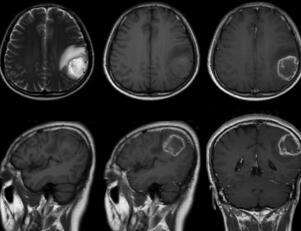

图1左顶叶见类圆形占位,整体呈等T1、长T2信号,其内混杂少许稍短T1短T2信号,病变周围包绕水肿信号带。增强扫描病变呈花环状强化,可见壁结节,病变大小约39mm×31mm×29mm

肿瘤边界不清楚,可呈弥漫性浸润生长,病变呈明显不均质状,瘤体内囊变、坏死、出血常见,钙化少见。前者多数呈低、等、混合密度,少数为等或低密度;后者多呈低或等密度为主的低、等混合密度。占位效应明显,瘤周可有明显血管源性水肿。可沿白质通道扩散,或沿室管膜、软脑膜和脑脊液种植转移。发生于胼胝体附近的肿瘤常累及中线两侧呈蝶翼状生长,尤多见于GBM。增强扫描多呈不规则环状(花环状)强化,少数为结节状、斑片状或环伴结节状强化。